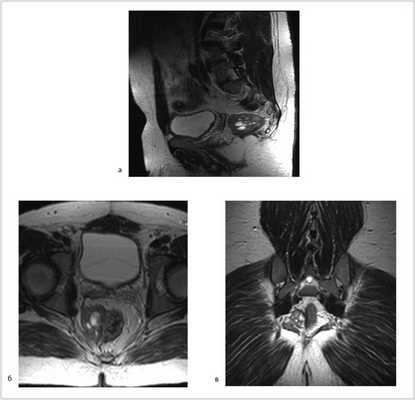

07.11.2012 выполнена цилиндрическая или экстралеваторная экстирпация прямой кишки. Через тазовую брюшину в мезоректальной клетчатке справа пальпируется верхний полюс опухоли, подрастающей к стенке прямой кишки, опухоль фиксирована к правой боковой стенке таза. Отдаленных метастазов нет (рис. 4).

Рис. 4. Этап операции. Ревизия опухоли.

Произведена мобилизация прямой кишки по левой и задней полуокружности, а также пресакрально до мышц тазового дна с соблюдением всех онкологических правил (рис. 5). По левой боковой стенке таза опухолевая капсула интимно прилежит к внутренней подвздошной вене и артерии, острым путем последняя мобилизована от магистральных сосудов.

Рис. 5. Этапы операции. а — мобилизация слева; б — мобилизация справа.

Далее сигмовидная кишка пересечена на уровне ее дистальной трети, а прямая кишка погружена в малый таз, при этом тазовая брюшина ушита над заглушенной культей прямой кишки. Затем сигмовидная кишка забрюшинно выведена в левом боковом отделе живота на переднюю брюшную стенку и сформирована плоская колостома, после чего брюшная полость ушита наглухо послойно (рис. 6).

Рис. 6. Этапы операции. а — ушивание тазовой брюшины; б — сигмостома.

Далее больной перевернут на живот в положении по типу «перочинного ножа» (рис. 7).

Рис. 7. Положение больного на столе (а). Вид операционного поля промежности (б).

После обработки операционного поля мобилизация прямой кишки продолжена из широкого промежностного доступа. Выполнено ушивание заднего прохода кисетным швом, намечены края резекции. В проекции крестцово-копчикового сочленения кожа и подкожная жировая клетчатка рассечены до задней крестцово-копчиковой связки. Последняя пересечена в поперечном направлении. Выполнена ампутация копчика с последовательным пересечением передней крестцово-копчиковой и крестцово-прямокишечной связок (рис. 8).

Рис. 8. Этапы операции. а — ушивание ануса; б — рассечение кожи и подкожной жировой клетчатки; в — пересечение крестцово-копчиковых связок.

Далее прямая кишка с опухолью в едином блоке мобилизована острым путем от предстательной железы и правой стенки таза, после чего выполнена цилиндрическая брюшно-промежностная экстирпация прямой кишки. Малый таз дренирован двумя силиконовыми дренажами и ушит наглухо (рис. 9).

Рис. 9. Этапы операции. а — мобилизация простаты; б — дренирование малого таза; в — конечный вид раны.